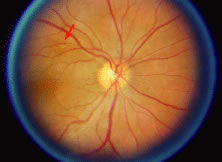

The ARN patient typically presents with progressive visual blurring in one or both eyes occurring over several weeks. These patients often are initially treated with corticosteroids, antitoxoplasmosis drugs, and other medications before arriving at the correct diagnosis. Examination reveals a prominent anterior uveitis that may be granulomatous or nongranulomatous (Fig. 1). Inflammatory signs may be prominent and cause severe pain (Fig. 2). The uveitis may be diffuse and so severe that it causes proptosis. These signs, and the diffuse vitreitis that makes the view of the retina difficult, may contribute to the high degree of delayed and/or misdiagnosis that occurs in the early stages of the disease. Significant vitreous cellular infiltration is seen in the presence of retinitis that is manifest by opacification of the retina, often most prominently in the periphery. Posterior pole involvement may include retinitis, as well as inflammation of the optic nerve head. Optic neuropathy might be the first sign of ARN with subsequent development of other retinal manifestations.8 Ultrasonography and computed tomography (CT) might be helpful in cases of ARN associated with optic nerve edema revealing enlargement of the optic nerve sheath.9 Even in ARN patients who are not immunocompromised and who have no clinical evidence of encephalitis, magnetic resonance imaging of selected cases has shown lesions of the lateral geniculate, optic tracts, and chiasma, which suggests that the virus spreads through the central nervous system (CNS) by axoplasmic transport from the retinal ganglion cells.10 A secondary retinal vasculitis is common, often accompanied by a mild number of retinal hemorrhages. Days to weeks after onset of the infection, the discrete peripheral lesions typically coalesce into a white or yellow ring of infected retina, and the associated vasculature is obliterated (Fig. 3). Necrotic retina desquamates into the vitreous resulting in vitreous sheets.3,6 Eventually, most untreated eyes can be expected to develop retinal detachment resulting from development of multiple full-thickness retinal breaks accompanied by traction or exudation.11 Giant retinal pigment epithelial tears have also been reported.12